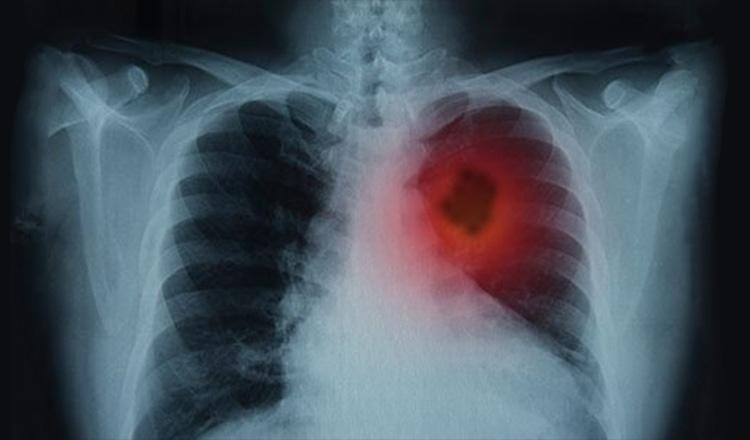

ফুসফুসের ক্যান্সারের প্রাথমিক লক্ষণ

প্রতিকী ছবি